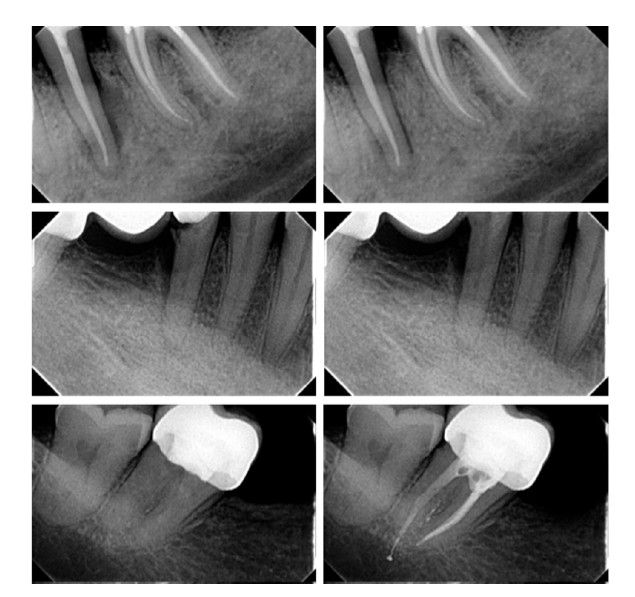

Para minimizar posibles sesgos derivados de la memoria o del contexto conversacional, cada par se evaluó en 30 sesiones independientes (“nueva conversación”), distribuidas en distintos momentos del día, siguiendo la metodología descrita por Freire y cols. 14. En total, se realizaron 240 registros (8 pares × 30 repeticiones). Algunos ejemplos de las radiografías modificadas pueden observarse en la Figura 1.

Cada radiografía se exportó a formato JPG para su manipulación mediante el software Adobe Photoshop 2021 (Adobe Inc., San José, CA, EE. UU.). Se realizó una modificación diferente en cada radiografía. Las modificaciones efectuadas en cada radiografía se detallan en la Tabla.